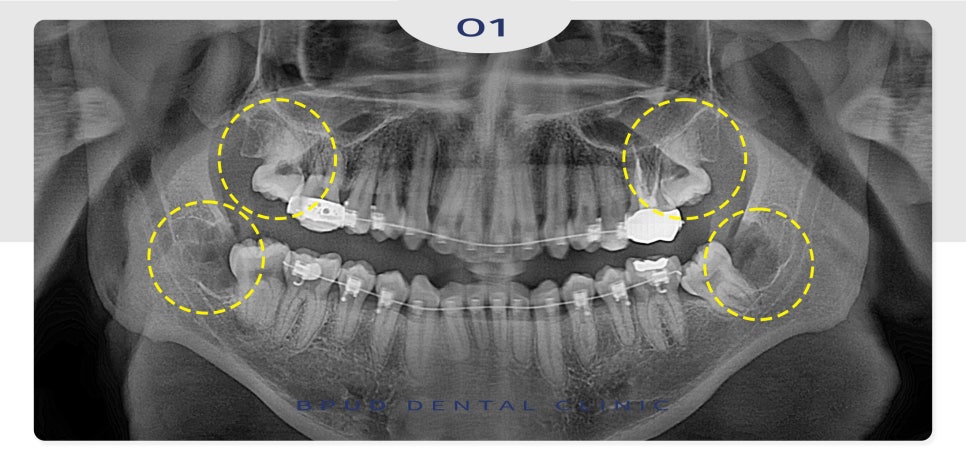

오늘은 양쪽에 매복되어 있는

사랑니 4개 모두 발치를 진행하신

부평동치과 환자분을

소개해 드리려고 합니다.

악궁이 작아서 치아 교정을 진행 중이신

상태로 사랑니 또한 완전히 매복되어 있었고

앞쪽 치아에 걸려 난이도가

매우 높은 케이스였는데요.

24.12.03

완전 매복 고난이도 사랑니로

신경에 완전히 닿아 있어 신경 손상의

위험이 높은 케이스였으나 문제없이

발치 계획을 수립하였습니다.